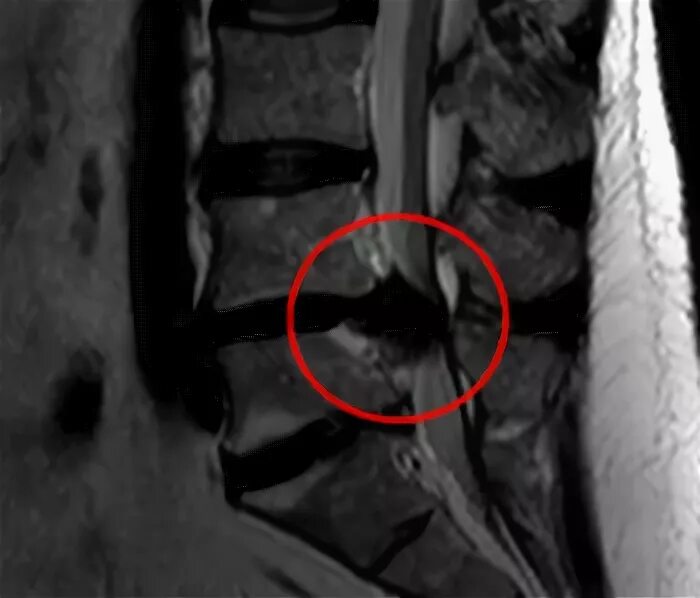

Грыжа 4 5